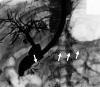

IgG4-related sclerosing cholangitis (IgG4-SC) is a distinct type of cholangitis frequently associated with autoimmune pancreatitis and currently recognized as a biliary manifestation of IgG4-related disease. Although clinical diagnostic criteria of IgG4-SC were established in 2012, differential diagnosis from primary sclerosing cholangitis and cholangiocarcinoma is sometimes difficult. Furthermore, no practical guidelines for IgG4-SC are available. Because the evidence level of most articles retrieved through searching the PubMed, Cochrane Library, and Igaku Chuo Zasshi databases was below C based on the systematic review evaluation system of clinical practice guidelines MINDS 2014, we developed consensus guidelines using the modified Delphi approach. Three committees (a guideline creating committee, an expert panelist committee for rating statements according to the modified Delphi method, and an evaluating committee) were organized. Eighteen clinical questions (CQs) with clinical statements were developed regarding diagnosis (14 CQs) and treatment (4 CQs). Recommendation levels for clinical statements were set using the modified Delphi approach. The guidelines explain methods for accurate diagnosis, and safe and appropriate treatment of IgG4-SC.